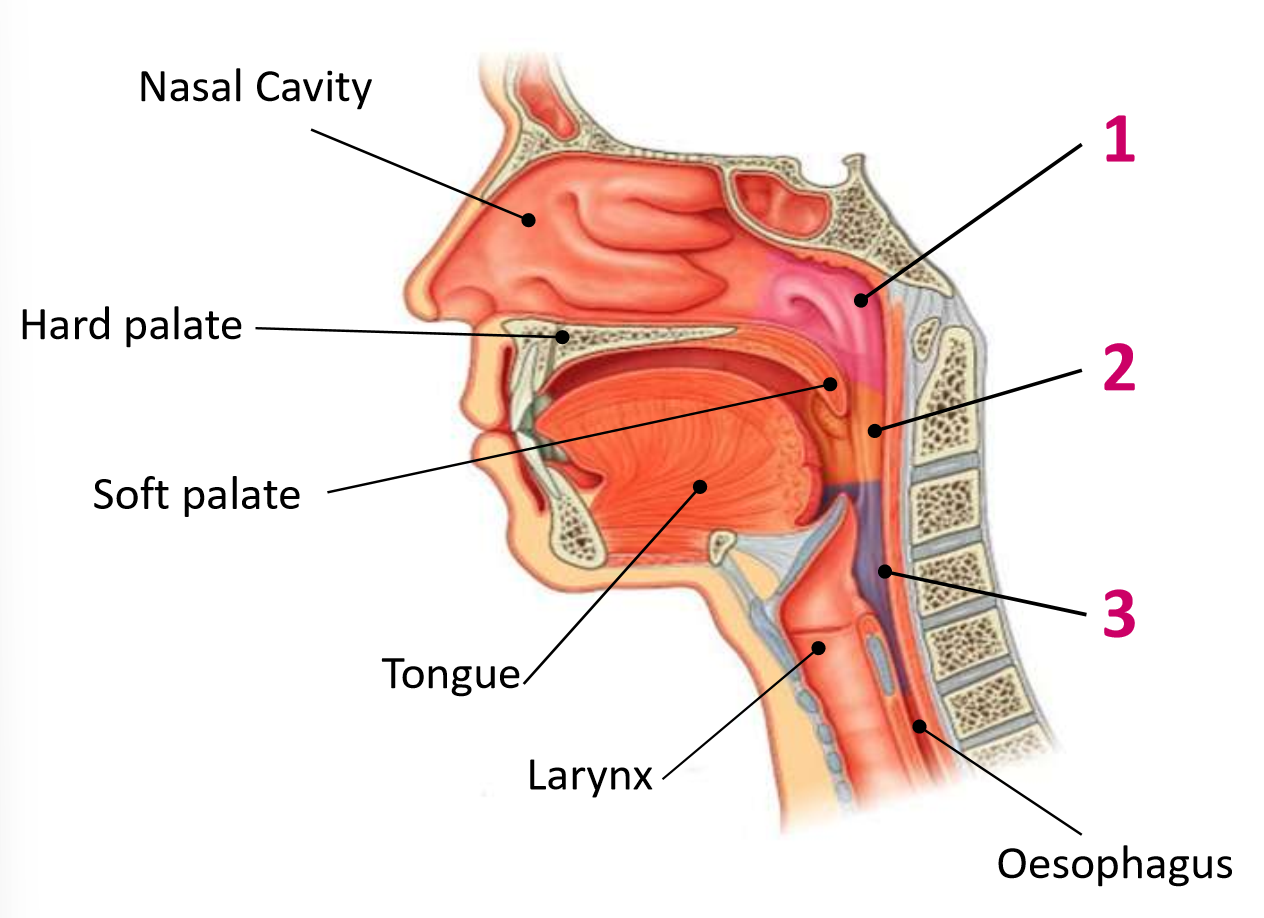

Which area of the head and neck do 1, 2, and 3 make?

pharynx

What region is 1?

nasopharynx

What region is 2?

oropharynx

What region is 3?

laryngopharynx